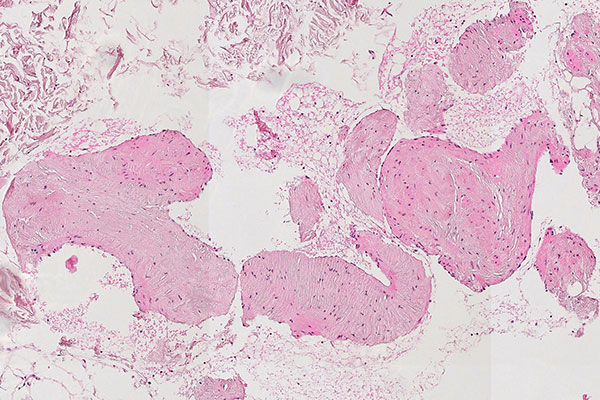

Histopathologischer Schnitt; Hämatoxylin-Eosin-Färbung (HE), 90-fache Vergrößerung des Stanzzylinders. Stanzzylinder mit Anteilen der venösen Malformation mit dicht gelagerten, irregulär konfigurierten, großkalibrigen venösen Gefäßanschnitten. Diese erscheinen nicht tubulär, wie bei einem normalen Gefäßanschnitt, sondern wie „umgestülpt“. Das Lumen ist solide und das Blut überall außenherum.

Histopathologischer Schnitt; Hämatoxylin-Eosin-Färbung (HE), 160-fache Vergrößerung des Stanzzylinders. Hier ist gut erkennbar, dass die eigentlichen irregulären, blutgefüllten Räume der venösen Malformation nicht solide sind, sondern teilweise mit Erythrozyten gefüllte „Leerräume“. Die Endothelauskleidung entspricht damit der äußeren Begrenzung der sichtbaren Läsion.

Das rein histopathologische Erkennen einer Läsion unter dem Mikroskop als venöse Malformation ist ohne entsprechende klinische Angaben und entsprechende Fragestellung kaum möglich. Dennoch gibt es gute Hinweise, die immunhistologisch und morphologisch eine venöse Malformation charakterisieren.

Die venöse Malformation ist schwammartig blutgefüllt ohne echte solide Anteile, ähnlich einem Schweizer Käse mit viel Luft (Luftlöcher = blutgefüllte Hohlräume; Käse = dysplastische, venenartige Wandstrukturen). Die eigentlichen dysplastischen Venenwände machen also in der blutgefüllten Gesamtläsion nur einen Bruchteil des Volumens aus und erscheinen meist nicht rohrförmig wie ein Gefäß, sondern fuchsbauartig irregulär verzweigt.